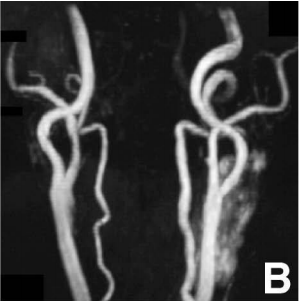

术后复查的MR血管造影显示:原来那个27mm的动脉瘤消失得无影无踪!左侧颈内动脉的管腔恢复通畅,困扰孙阿姨的颈部搏动感也随之消失。

术后磁共振血管造影显示动脉瘤消失,颈动脉通畅